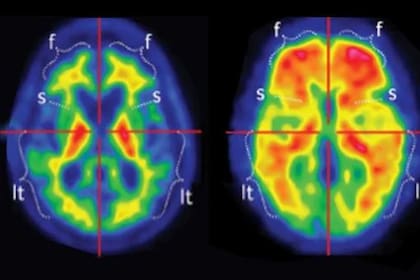

En el cerebro, el Alzheimer se caracteriza por la disfunción de dos proteínas, la beta amiloide y la tau, que forman placas y ovillos que dañan a las neuronas. Las placas amiloides pueden aparecer hasta 20 años antes de que comiencen los síntomas de demencia, mientras que los ovillos de tau aparecen más tarde, generalmente coincidiendo con el inicio del deterioro cognitivo.

Un diagnóstico de Alzheimer se basa, en parte, en la presencia de placas amiloides en el cerebro. Tradicionalmente eso se confirmaba mediante tomografías por emisión de positrones (PET) y análisis de líquido cefalorraquídeo, pero esas pruebas son costosas e invasivas, y muchos pacientes no acceden a ellas. Por eso los investigadores buscan un análisis de sangre que funcione como herramienta diagnóstica.

Pero los investigadores descubrieron que los análisis de sangre que miden una forma modificada de tau pueden ser un buen indicador de la acumulación de amiloide en el cerebro. Esto se debe a que, si bien los ovillos de tau aparecen más tarde, la proteína tau comienza a modificarse y volverse disfuncional casi al mismo tiempo que se forman las placas amiloides. Las pruebas actualmente disponibles se identifican con un número, como pTau181 o pTau217, que indica el sitio de la modificación en la proteína tau.